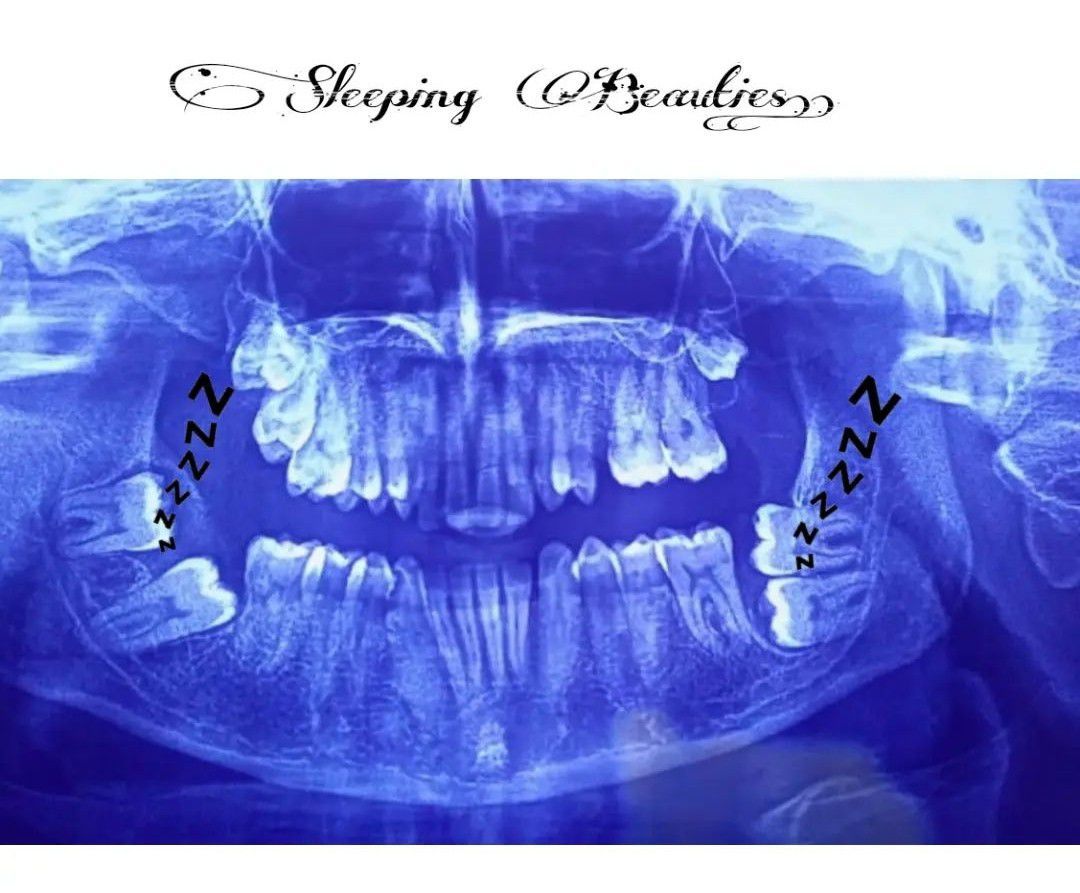

Sleeping Beauties

A rare presentation of impacted second and third molars often called sleeping beauties.